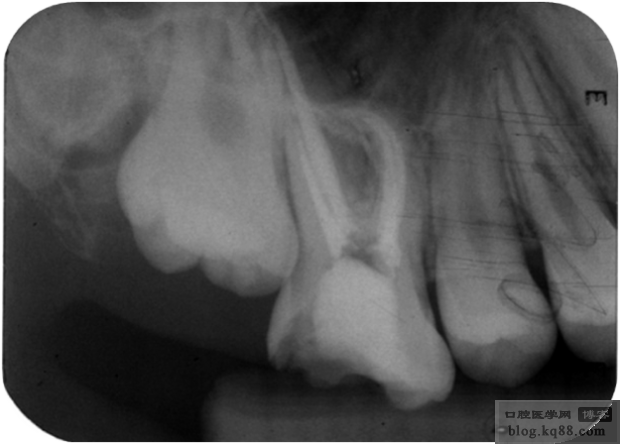

術(shù)前牙體及根管情況

近中根管彎曲明顯為25°以上,揭去髓頂探查根管,因根管彎曲度大,首先選用6-8號銼預(yù)彎,盡量選用新銼,不求一次探至全長。疏通根管,1.選用10-15號K銼預(yù)彎后進行管疏通。2根管口預(yù)備機用鎳鈦SX號。3彎曲上段采用根管馬達預(yù)備,下段采用手動預(yù)備。手動預(yù)備至25號,采用逐步后退法。預(yù)備完成。